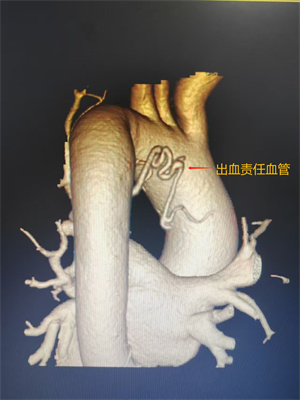

������үү����������71�꣬��Ѫ3���ࡱ��Ժ��סԺ�ڼ侭ҩ�ﱣ������Ч��Ƿ�ѣ�ͻ����Ѫ���أ�ͼ1���������½���93%���ң����Σ��������Ѫ����ƻ������֧���ܶ������ѳ�Ѫ���������м���BAE���ơ�

���߸��䣬����ƫ�ͣ���֧���ܶ�������϶࣬���г�ѡ���ѣ���������������ʱ�䣬�����ѶȽϴ���ǰ������Ѫ������Ŷӽ�ϻ�����������CTA����λ����ά�ؽ�ͼ��������Ѫ����Ѫ�ܵĿ���λ�ã���Ч���������г�ѡĿ��Ѫ��ʱ�䡣�����ڳ�ѡ��Ѫ����Ѫ�ܺ���PVA�������ϵ���Ȧ�Գ�Ѫ֧���ܶ������ɽ��о�˨����������Ӱ��ʾԭ��Ѫ����Ѫ����ʧ������˳����ɣ����߿�Ѫ֢״���Ի��⣬����ָ����ã�������������쿵����Ժ��